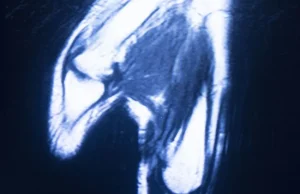

Resonancia magnética abierta de mano

La resonancia magnética (RM) es una herramienta indispensable en el diagnóstico de diversas condiciones médicas. En el caso de la mano, la RM abierta ofrece una evaluación detallada sin causar claustrofobia a los pacientes. Esto es especialmente útil para diagnosticar problemas como la artritis o lesiones en los tendones Vamos a ver cómo se utiliza … Sigue leyendo Resonancia magnética abierta de mano